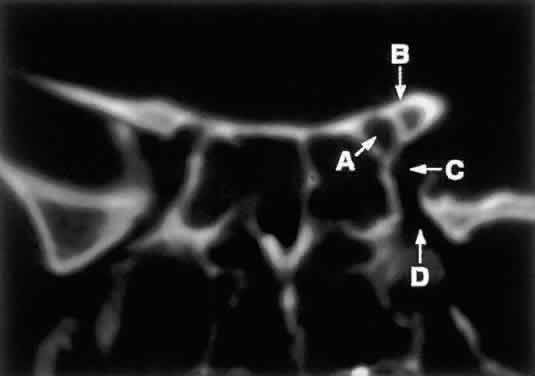

to lesions of the optic nerve (glioma) or nerve sheath (meningioma).  Fig. 8. Coronal CT image (bone window) of the orbital apex in a patient with facial

trauma. Note the position of the posterior orbital foramina. The

optic canal (A) is always seen in conjunction with the laterally adjacent anterior clinoid

process (B) on both axial and coronal views. Slightly lower, the superior orbital

fissure (C) communicates with the CS, found directly behind it. The inferior orbital

fissure (D) provides communication through the orbital floor with the pterygopalatine

fossa. Fig. 8. Coronal CT image (bone window) of the orbital apex in a patient with facial

trauma. Note the position of the posterior orbital foramina. The

optic canal (A) is always seen in conjunction with the laterally adjacent anterior clinoid

process (B) on both axial and coronal views. Slightly lower, the superior orbital

fissure (C) communicates with the CS, found directly behind it. The inferior orbital

fissure (D) provides communication through the orbital floor with the pterygopalatine

fossa.